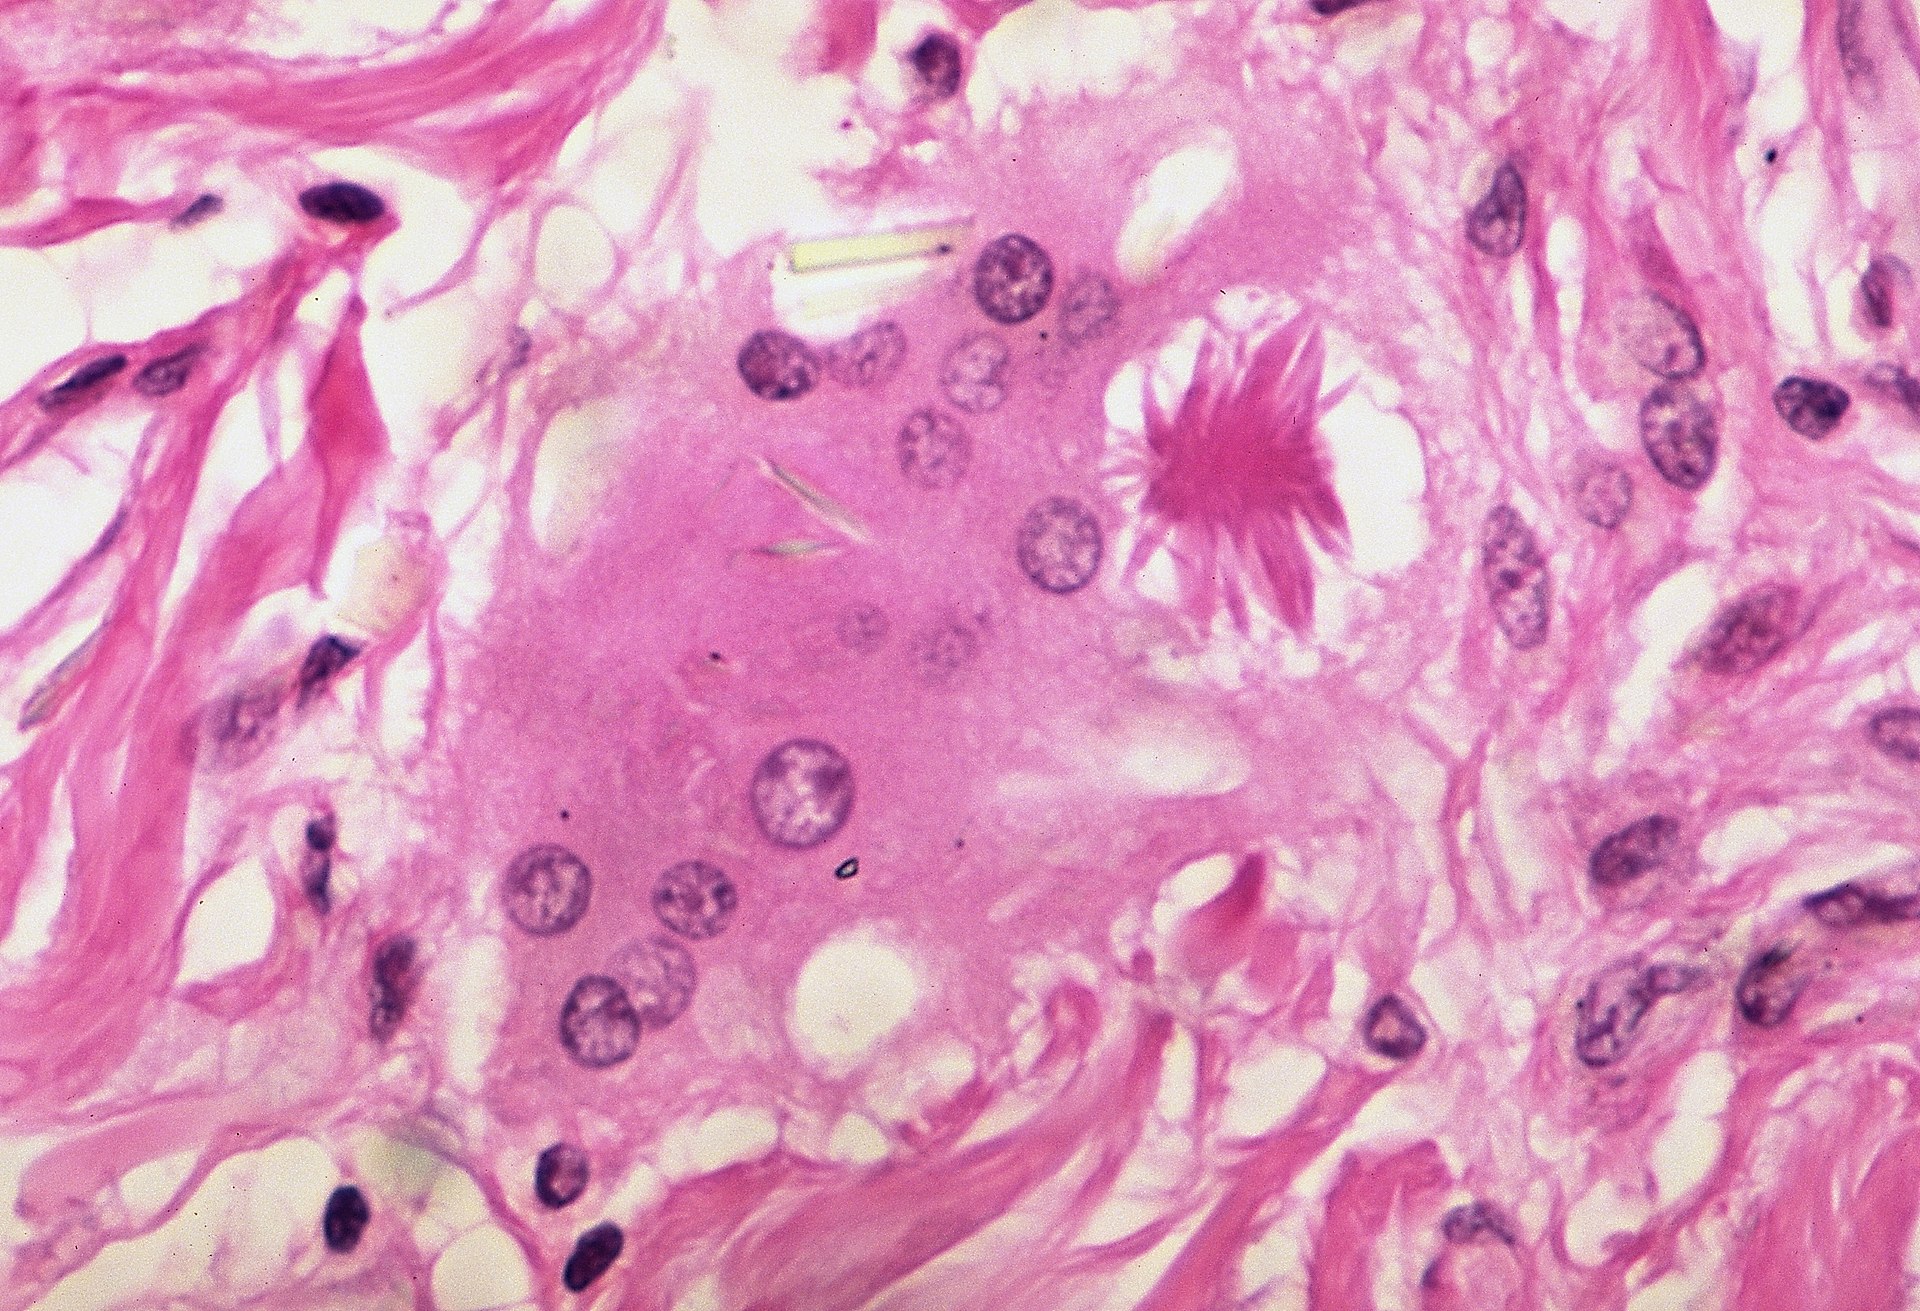

Histology of sarcoidosis includes naked granulomas and stellate inclusions (‘asteroid bodies’) are often seen within giant cells of the granulomas.